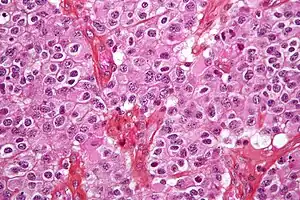

However, these techniques cannot alone diagnose high- versus low-grade gliomas, and thus the definitive diagnosis of brain tumor should only be confirmed by histological examination of tumor tissue samples obtained either by means of brain biopsy or open surgery. The histological examination is essential for determining the appropriate treatment and the correct prognosis. This examination, performed by a pathologist, typically has three stages: interoperative examination of fresh tissue, preliminary microscopic examination of prepared tissues, and follow-up examination of prepared tissues after immunohistochemical staining or genetic analysis.

Pathology

Tumors have characteristics that allow the determination of malignancy and how they will evolve, and determining these characteristics will allow the medical team to determine the management plan.

Anaplasia or dedifferentiation: loss of differentiation of cells and of their orientation to one another and blood vessels, a characteristic of anaplastic tumor tissue. Anaplastic cells have lost total control of their normal functions and many have deteriorated cell structures. Anaplastic cells often have abnormally high nuclear-to-cytoplasmic ratios, and many are multinucleated. Additionally, the nucleus of anaplastic cells is usually unnaturally shaped or oversized. Cells can become anaplastic in two ways: neoplastic tumor cells can dedifferentiate to become anaplasias (the dedifferentiation causes the cells to lose all of their normal structure/function), or cancer stem cells can increase their capacity to multiply (i.e., uncontrollable growth due to failure of differentiation).

Atypia: an indication of abnormality of a cell (which may be indicative of malignancy). Significance of the abnormality is highly dependent on context.[51]